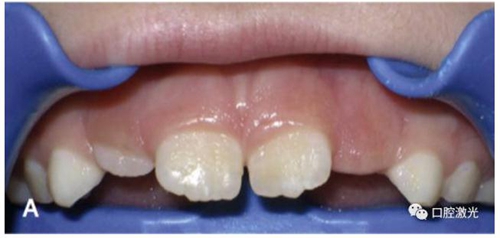

智齒盲袋切除

許多患者由于智齒盲袋的存在妨礙了正畸治療的進行。通過口腔激光進行盲袋切除后,立即可以繼續(xù)正畸治療。需要注意的是,激光盲袋切除是為數(shù)不多幾個僅僅采取表麻可能不能滿足,而需要注射局部麻醉的手術(shù)。

A盲袋覆蓋了第二磨牙的中遠端

B激光盲袋切除后立即實施正畸治療